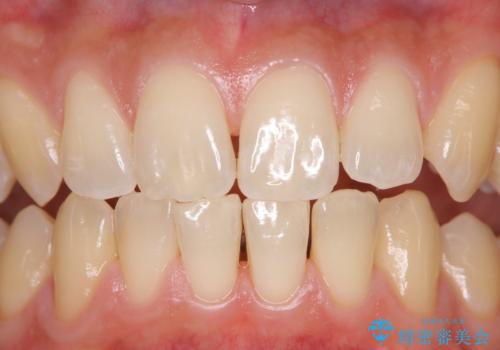

- 数年ぶりに歯科へ来院とのこと。全体的に歯のクリーニングをしてほしいとのことでした。

PMTC60分コースを行いました。